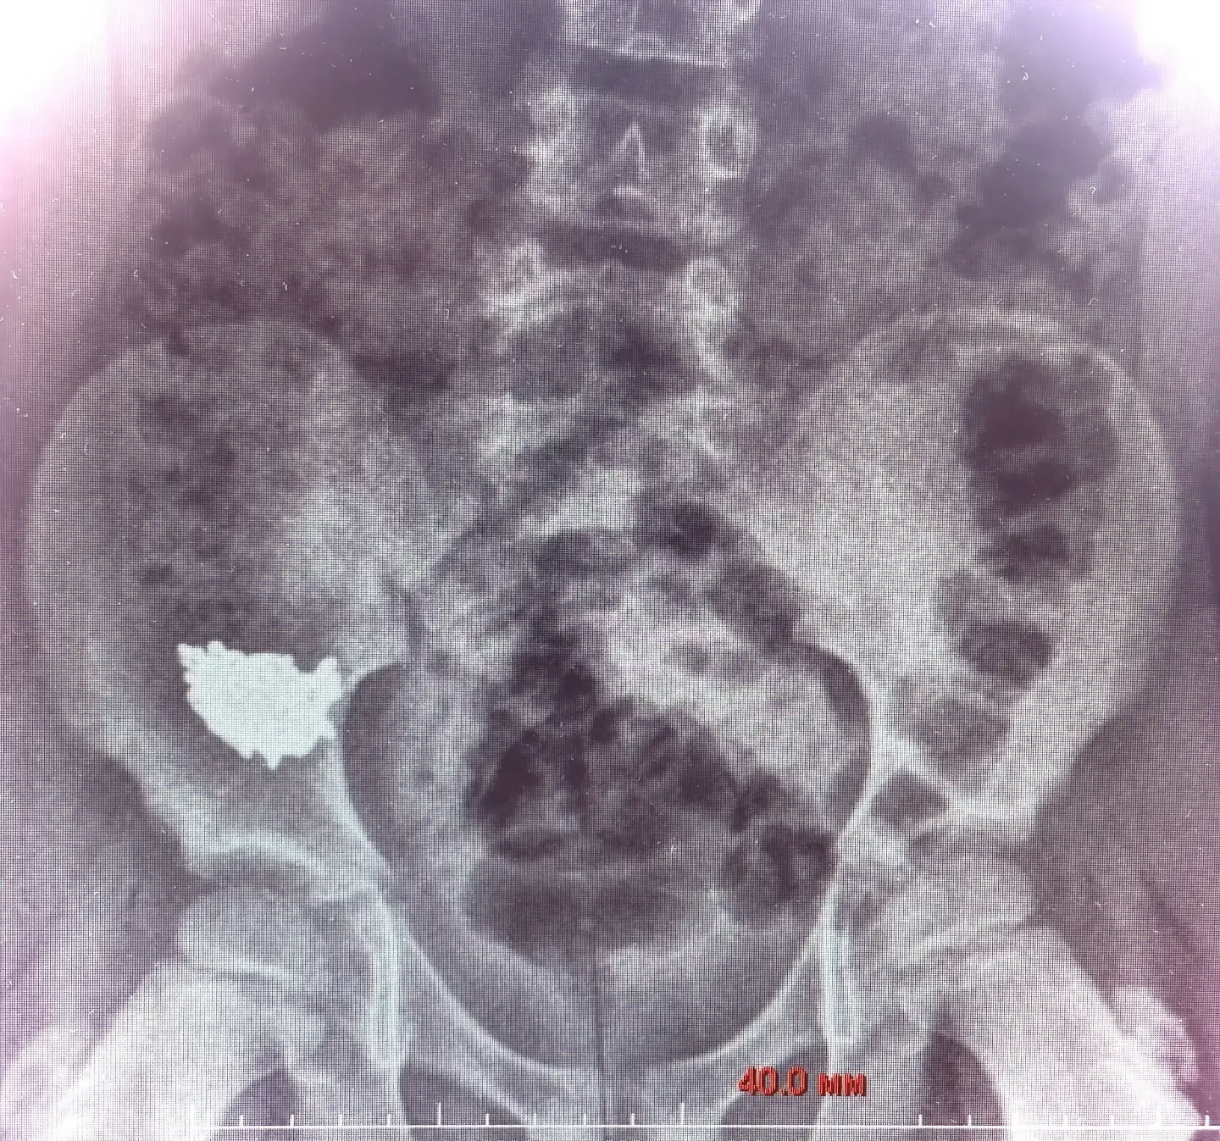

Родители обратились в приёмное отделение и сообщили о произошедшем. После рентгена медики установили, что инородное тело находится в правой подвздошной области. Ребёнка госпитализировали для наблюдения и консервативного лечения.

«Снимки на третьи и четвёртые сутки после обращения показали, что инородное тело не двигается по ЖКТ, находится без динамики в правой подвздошной области», — рассказал детский хирург Владимир Кораблёв.